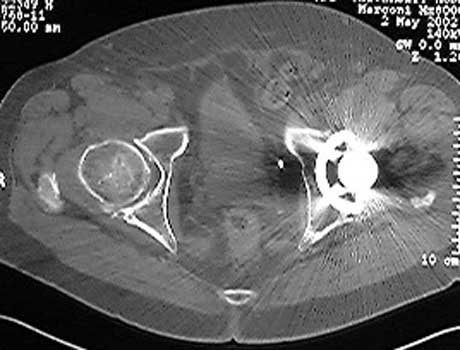

Mass in patient with modular endoprosthesis placed after resection of femur for osteosarcoma. Axial (fig A) and coronal reformatted images (fig B) clearly demonstrate mass adjacent to modular endoprosthesis. 14 gauge core needle biopsy performed under CT guidance (fig C) demonstrated recurrent osteosarcoma